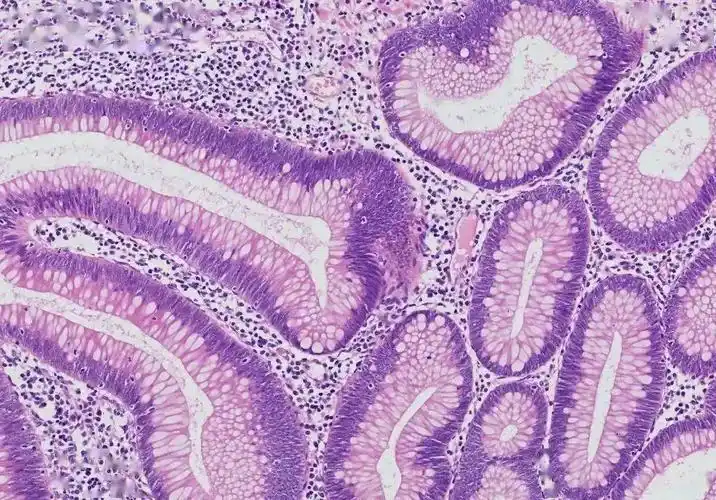

优秀病理切片分享本次会议邀请阳泉市第三人民医院心胸乳腺科主任王然